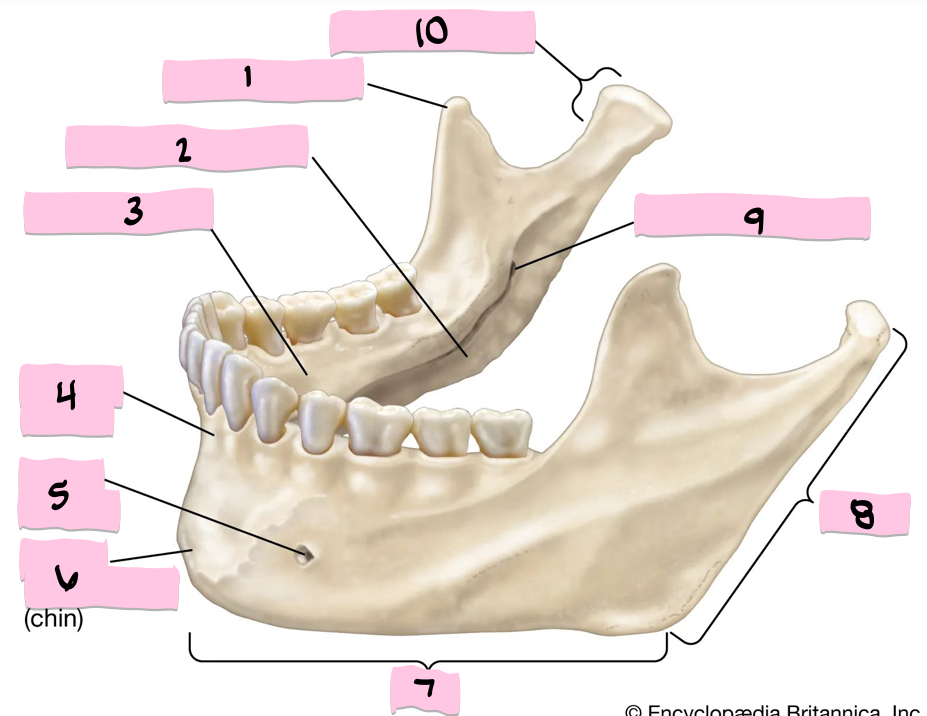

What is 1 pointing to?

Coronoid process

What is 2 pointing to?

Submandibular fossa

What is 3 pointing to?

Sublingual fossa

What is 4 pointing to?

Alveolar process

What is 5 pointing to?

Mental foramen

What is 6 pointing to?

Mental protuberance

What is 7 pointing to?

Body

What is 8 pointing to?

Ramus

What is 9 pointing to?

Mandibular foramen

What is 10 pointing to?

Condylar process